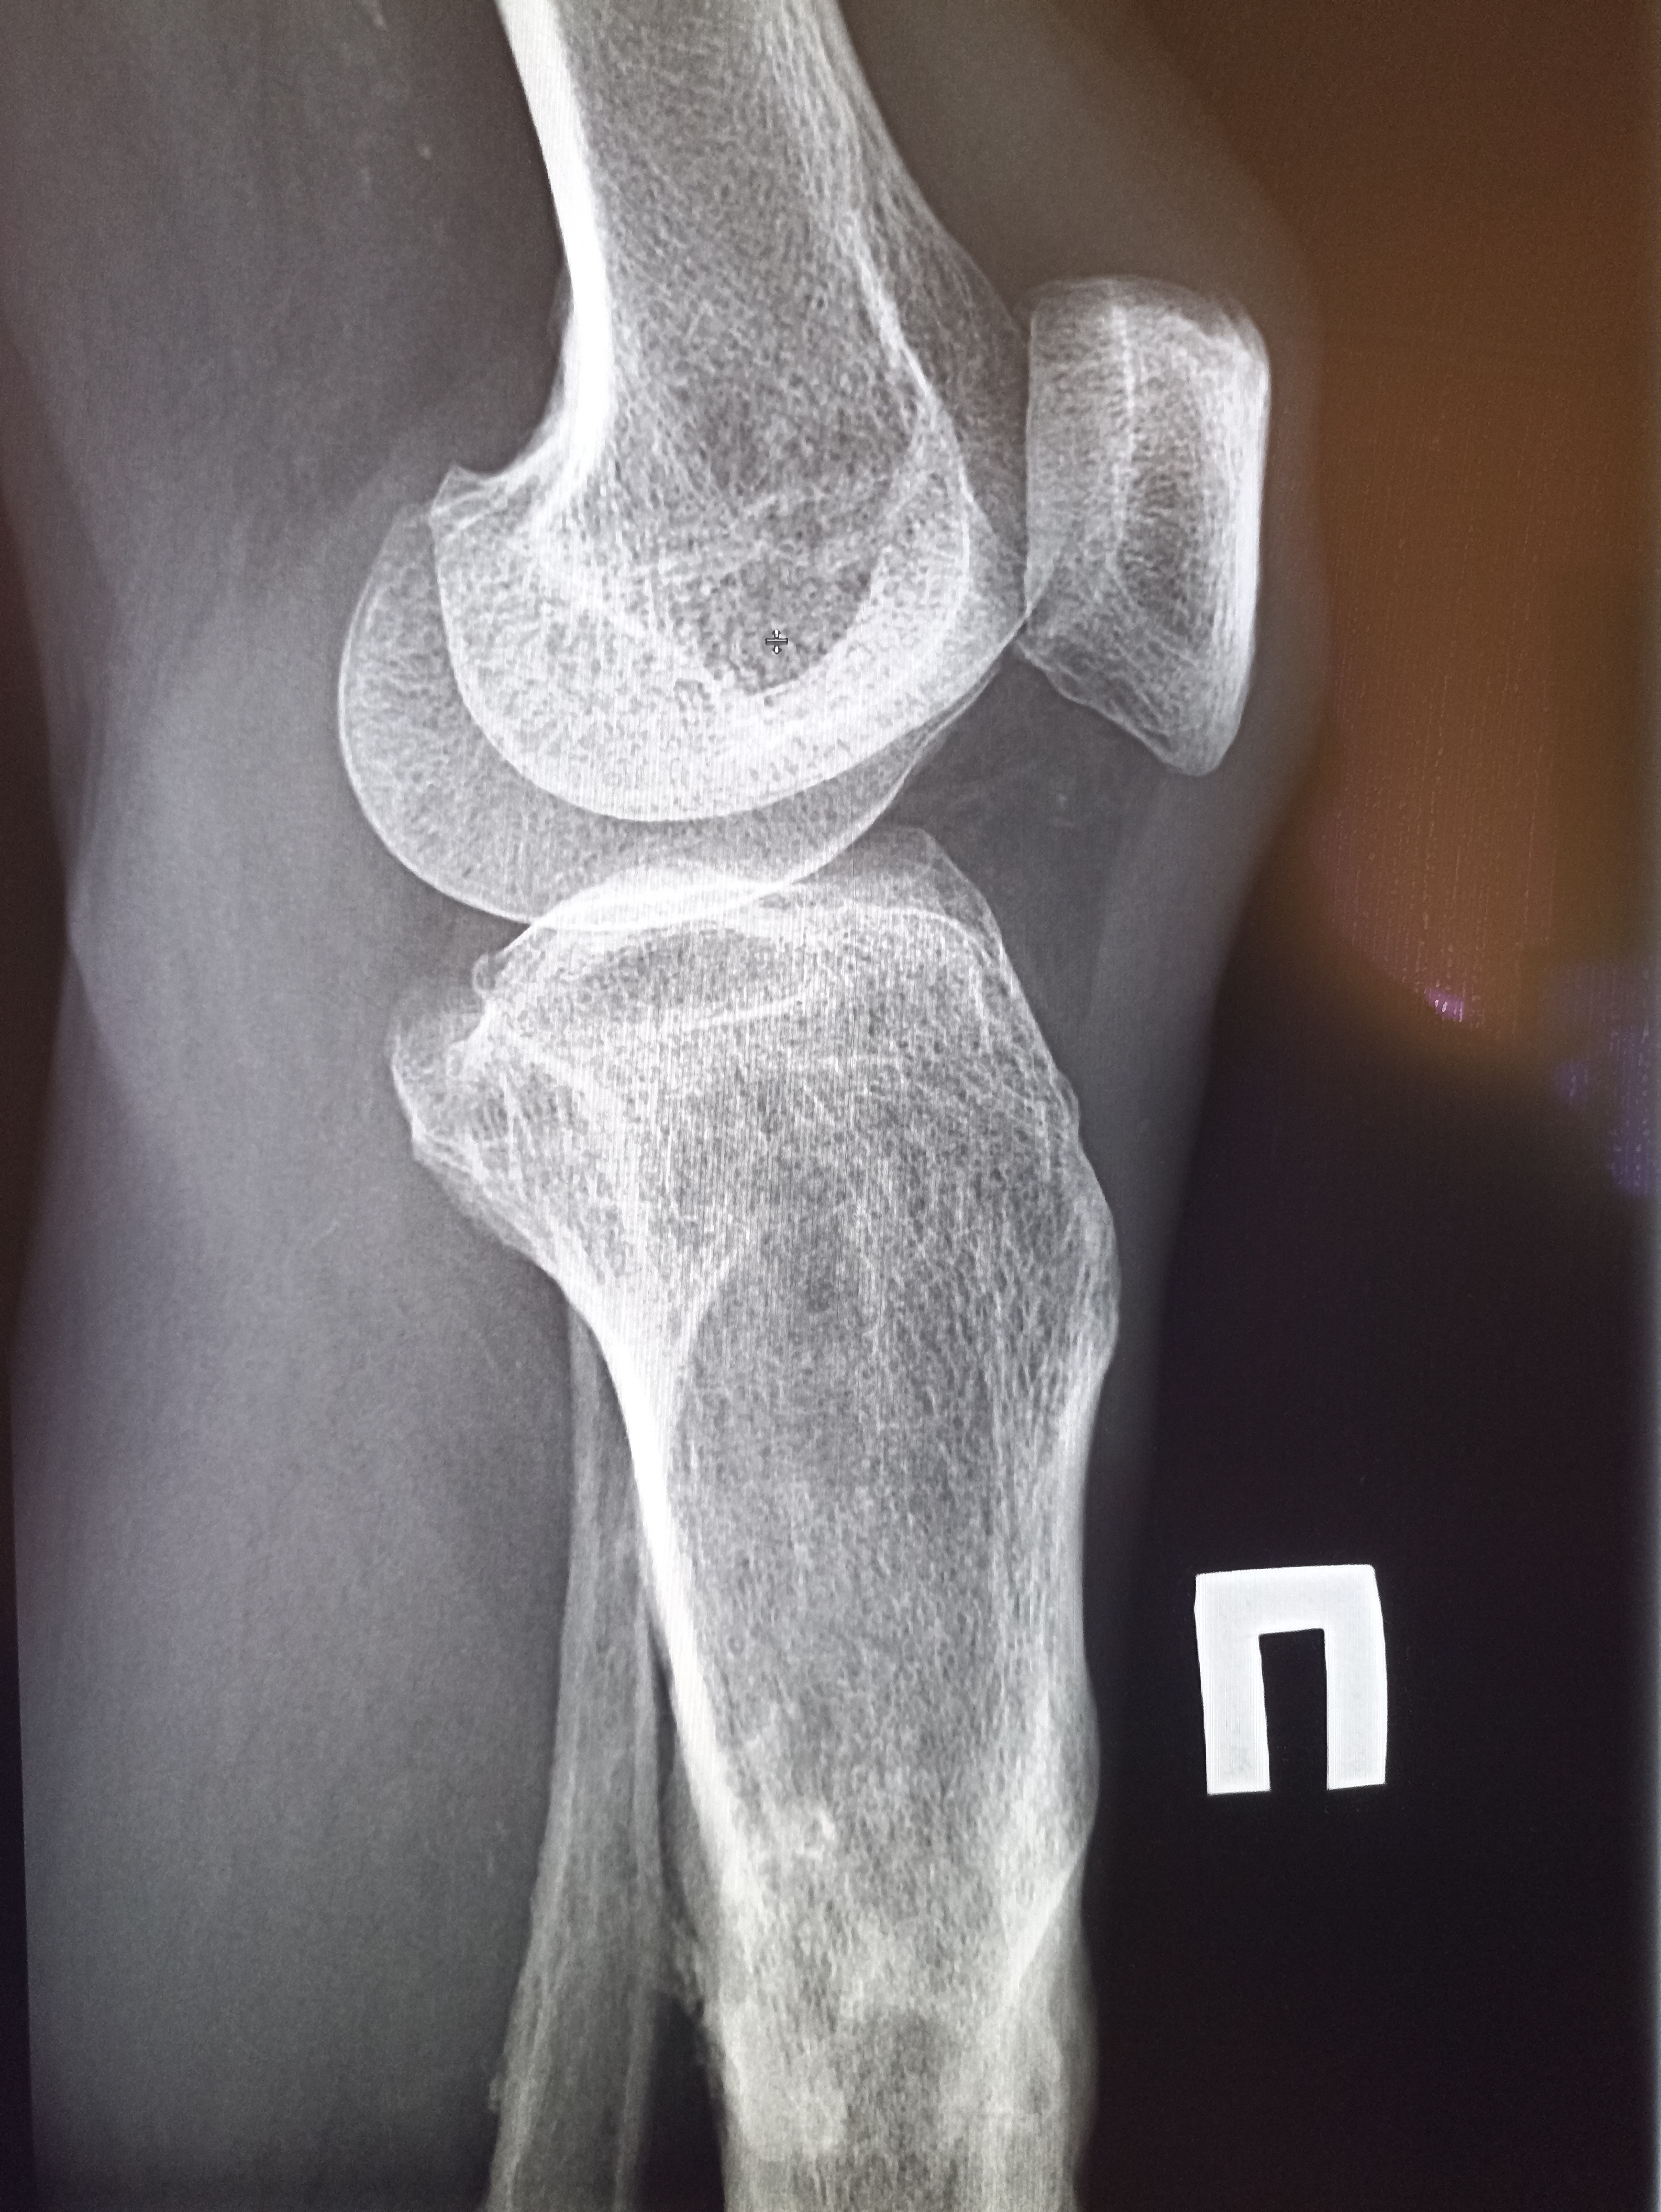

Здравствуй двачик, пишет вам простой рентгенолог из мухосранской поликлиники, сегодня я буду флексить зарплатой за ноябрь! Аж ПЯТЬДЕСЯТ ТРИ ТЫЩИ ПЕРЕВЕДУТ! С пруфом! А чего достигли вы? Ну и в доктора тож поиграем! Я буду вам картинки показывать, а вы пиздецомы находить! Найдите пиздецому на фтчк! Отчет еще по фог считать квартальный и годовой сегодня :-(